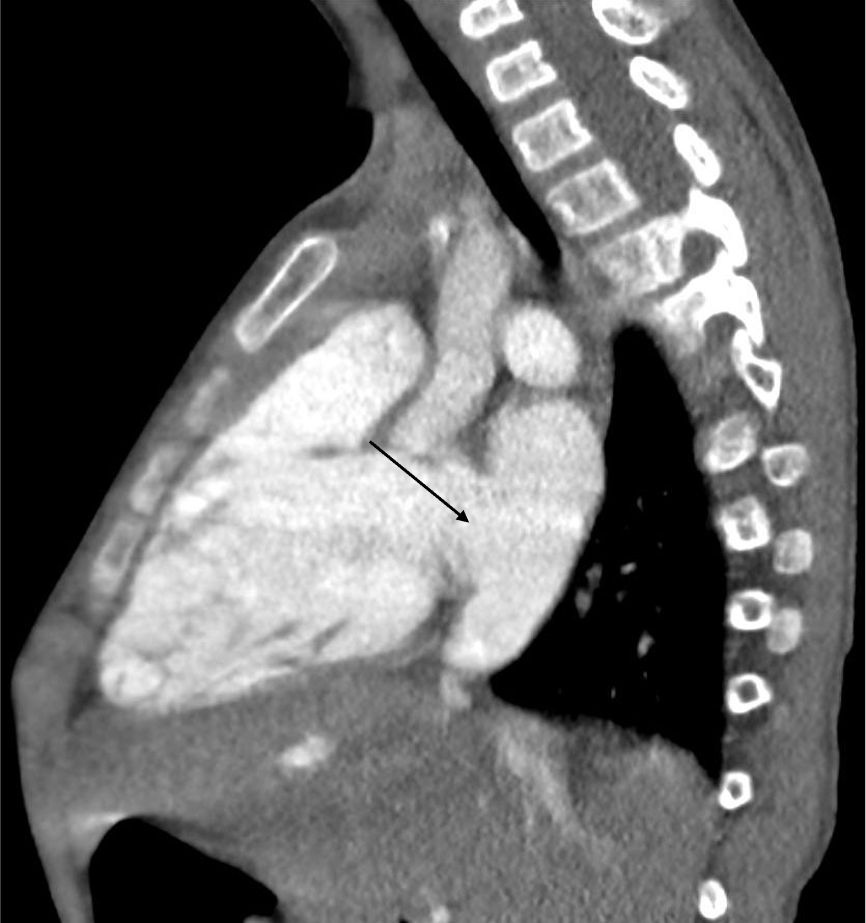

3歳、 男児、 9kg、 心房中隔欠損

染色体異常が判明している男児。肺炎で入院した際のレントゲンで右心系の拡大を指摘された。心臓超音波検査にて心房間の短絡が疑われた。心房中隔欠損症疑いの精査、肺静脈還流異常の除外目的で造影CT検査が施行された。

心房中隔欠損症は左右の心房に短絡を生じる先天性の病態である。欠損部位により、二次孔欠損、一次孔欠損および冠静脈洞欠損に大別される。まず身体所見、胸部レントゲン写真および心電図検査が行われ、解剖学的構造を評価するために、心エコー検査が施行される。心エコー検査で十分な情報が得られない場合、欠損孔の部位や形態を評価するために造影CTが施行される。最終的な治療方針の決定にはカテーテル検査が施行されることが多いが、あらかじめ病変の形態や解剖を把握するために造影CTは有用である。また肺静脈還流異常を合併することがあるため、その有無を評価することができる。短絡が小さいものについては経過観察が可能であるが、ある程度大きい病変に対しては治療が必要となる。治療はカテーテルによる閉鎖術、外科手術が挙げられる。カテーテルによる閉鎖術が選択される場合には、造影CTは治療計画用にも用いられる。その場合には、任意多断面再構成(MPR)やvolume rendering(VR)像などを活用する。